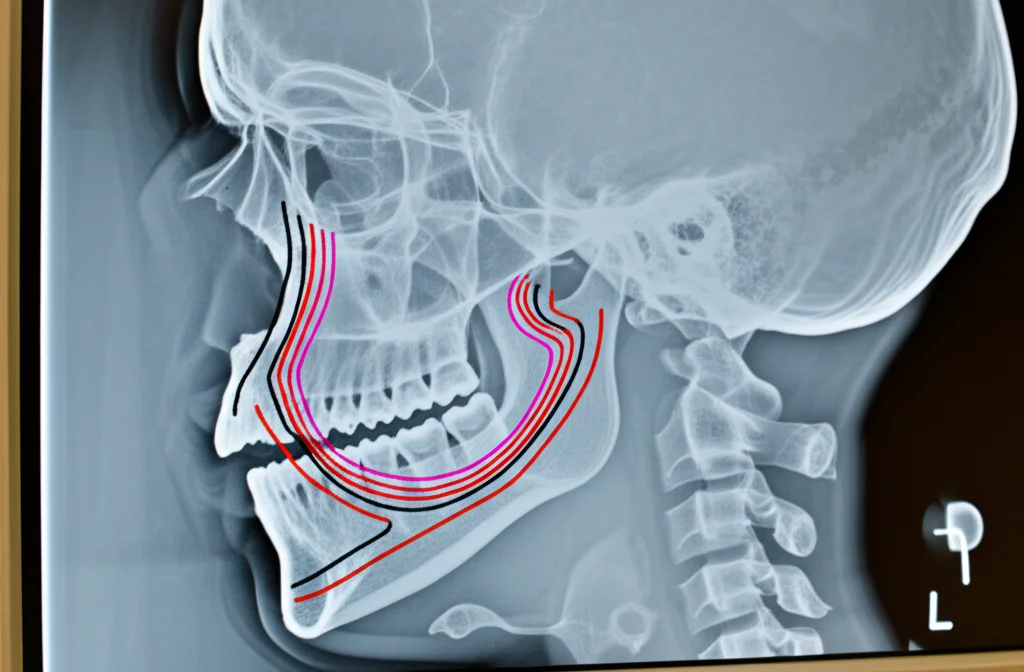

Anche l’analisi cefalometrica (la radiografia laterale del cranio) ha confermato i miglioramenti: una leggera riduzione dell’iperdivergenza facciale (grazie a una piccola rotazione antioraria della mandibola), un miglioramento della relazione scheletrica e, soprattutto, una significativa riduzione dell’inclinazione degli incisivi. Le radiografie hanno anche mostrato radici ben parallele e nessun segno di riassorbimento radicale, un ottimo segno!

Una cosa che trovo affascinante è la precisione che si può raggiungere oggi. Confrontando il risultato finale ottenuto con il setup digitale pianificato all’inizio del trattamento, la corrispondenza era altissima. Questo dimostra quanto siano potenti e affidabili i flussi di lavoro digitali in ortodonzia. E la paziente? Felicissima, non solo per il risultato ma anche per aver potuto affrontare il trattamento con un apparecchio praticamente invisibile. A distanza di 12 mesi dalla fine del trattamento, il risultato era perfettamente stabile.